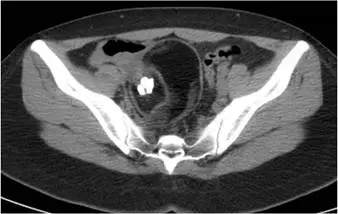

33 歲女性病患因腹痛接受電腦斷層檢查,發現下腹部有一病灶,內有鈣化成分如圖。其診斷為何:

本電腦斷層影像為骨盆腔橫切面,可見下腹部(骨盆腔內)有一明顯病灶,特徵如下:

- 高密度鈣化灶(hyperdense calcification):病灶內部可見明顯的高亮度鈣化成分,呈球狀/齒狀鈣化(globular/dentiform calcification),此為畸胎瘤最具特徵性的 CT 表現之一

- 囊性成分:病灶整體呈囊性低密度,內含上述鈣化

- 病灶位置:位於下腹部骨盆腔,符合卵巢來源病灶

- Rokitansky protuberance(Rokitansky 突起):成熟囊性畸胎瘤中典型可見此實性結節突入囊腔,本圖可見高密度結構,符合此特徵